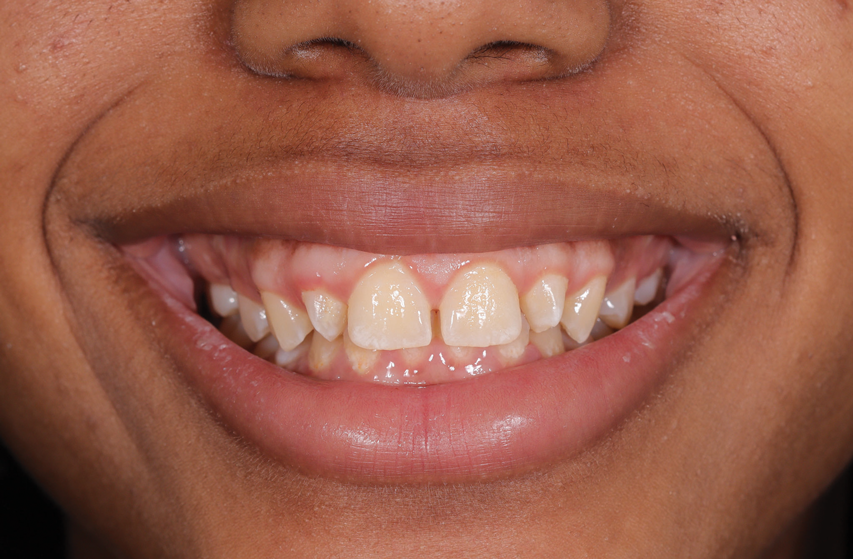

(32.) Posttreatment smile, left lateral smile, and right lateral smile photographs, respectively.

Figure 32

(33.) Posttreatment smile, left lateral smile, and right lateral smile photographs, respectively.

Figure 33

(34.) Posttreatment smile, left lateral smile, and right lateral smile photographs, respectively.

The rubber dam was removed from the mouth, and the excess material was removed with a No. 12B scalpel blade and a fine diamond bur. Next, the light-reflecting and light-deflecting zones were verified with a pencil and adjusted with finishing burs.11 The occlusion was then verified statically and dynamically using articulating paper and adjusted as needed. After finishing, the immediate postoperative polishing process was accomplished with a series of polishing discs followed by the use of a buffing disc with a diamond polishing paste (Figure 30). Eight days later, the patient returned to the office, and the final polishing was accomplished with polishing discs and diamond polishing paste (Figure 31 through Figure 35).

An assessment of the shape and shade of the final restorations was performed. It was noted that the incisal edges of the restored lateral incisors were not as white as those of the central incisors. Rather than adding additional stain to the lateral incisors, the patient expressed her desire to have some of the white staining removed from the central incisors using a resin infiltration technique after her orthodontic treatment. The final orthodontic treatment for the maxillary arch would involve closing the spaces in the anterior area, protracting the posterior teeth, and finishing in a Class II relationship. For the mandibular arch, the goal would only be to maintain the current positions of the teeth.